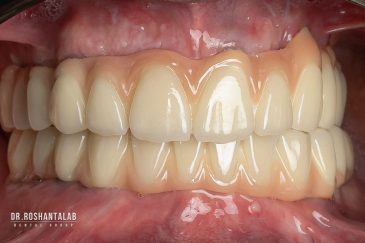

طراحی لبخند هالیوودی با متدهای لمینت سرامیکی دندان و کامپوزیت ونیر در کنار اصلاح فرم، خدمات بلیچینگ و روکش دندان، زیبایی چهره شما را تکمیل میکند.ترمیم دندان

انتخاب بهترین متخصص ایمپلنت که به تکنیکهای روز دنیا مسلط باشد، تضمینکننده سلامت فک و زیبایی لبخند شماست. در کلینیک دندانپزشکی دکتر روشنطلب، ما با بهرهگیری از تجهیزات دیجیتال در ۵ شعبه فعال (تهران، اصفهان، رشت و استانبول ترکیه)، خدمات تخصصی کاشت ایمپلنت دندان را برای بیمارانی که کیفیت و دقت برایشان اولویت دارد، ارائه میدهیم. در این متد، پروسه درمان با ظرافت بالا انجام شده؛ راهکاری ایدهآل برای کسانی که به دنبال درمان بدون درد با بالاترین نرخ موفقیت هستند.